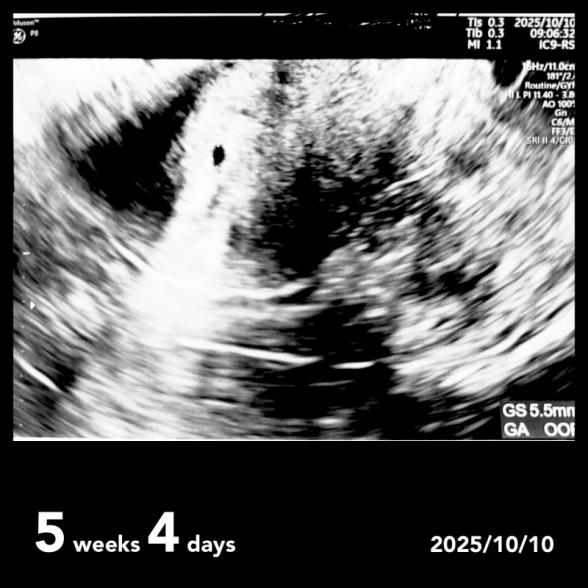

先週5w4dに胎嚢確認へ受診してきました。

胎嚢の大きさが5.5㎜でした。